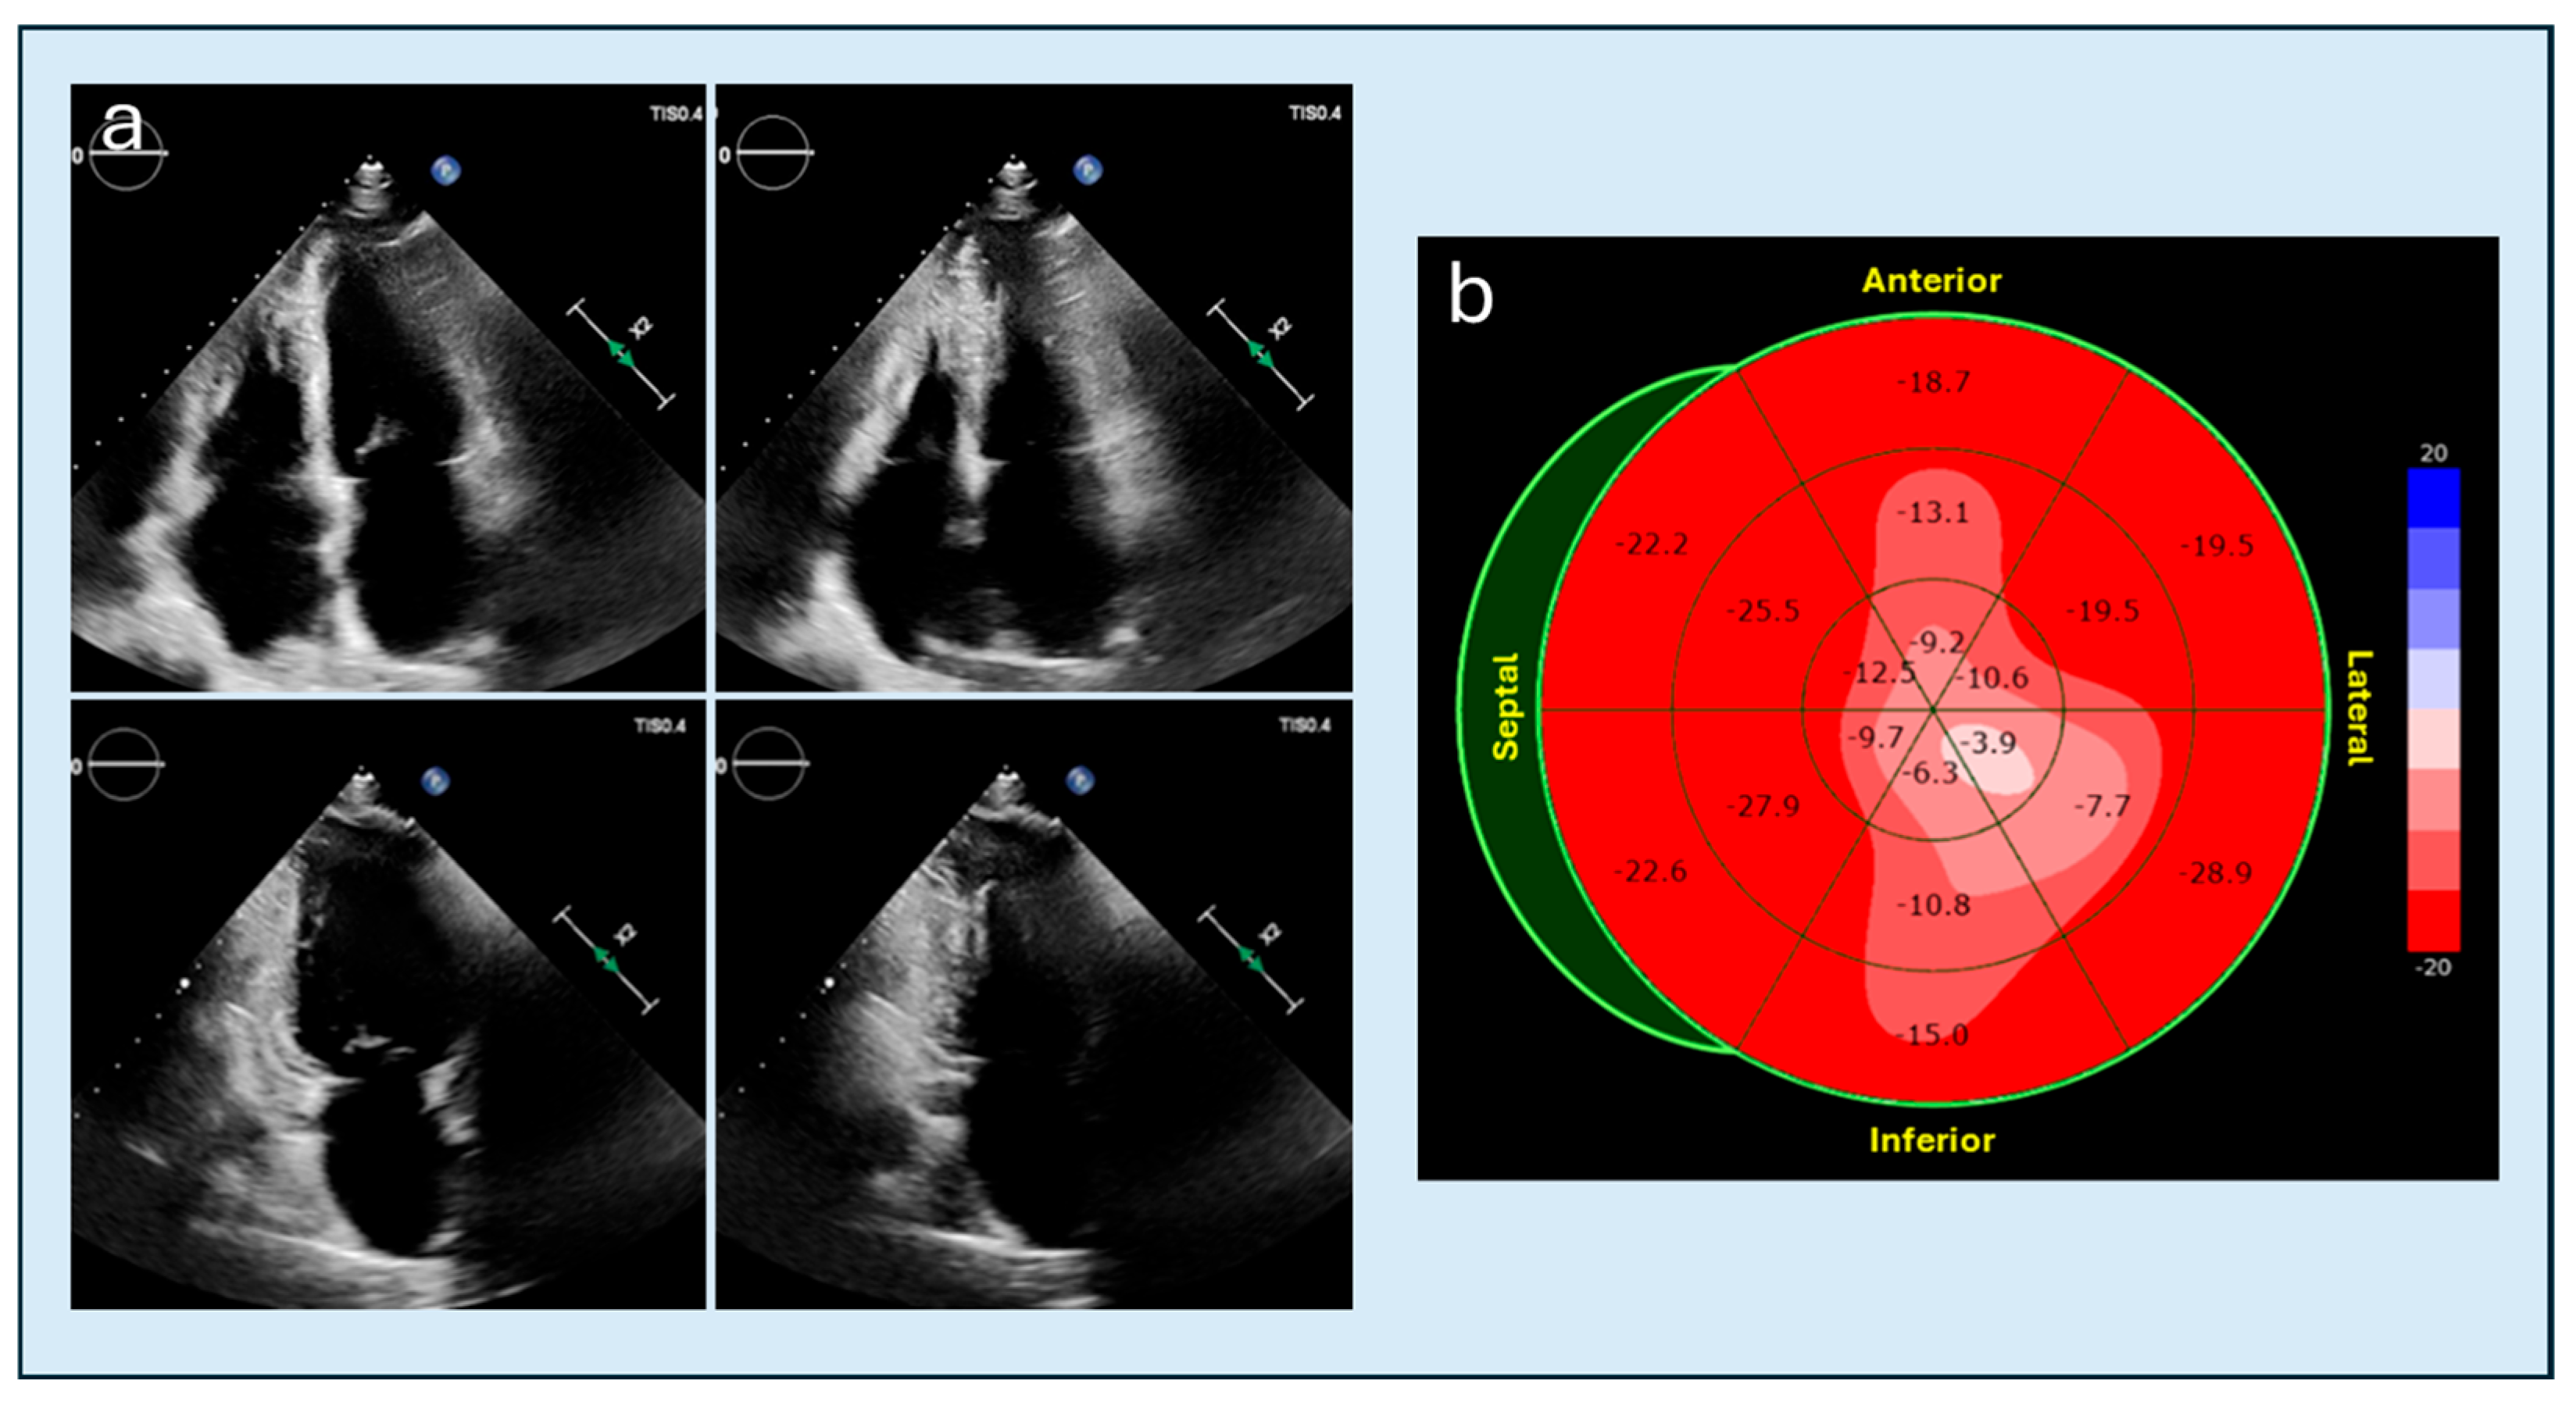

4.3. Speckle Tracking Imaging

- Saccheri, M.C.; Cianciulli, T.F.; Morita, L.A.; Méndez, R.J.; Beck, M.A.; Guerra, J.E.; Cozzarin, A.; Puente, L.J.; Balletti, L.R.; Lax, J.A. Speckle tracking echocardiography to assess regional ventricular function in patients with apical hypertrophic cardiomyopathy. World J. Cardiol. 2017, 9, 363–370. [Google Scholar] [CrossRef] [PubMed]